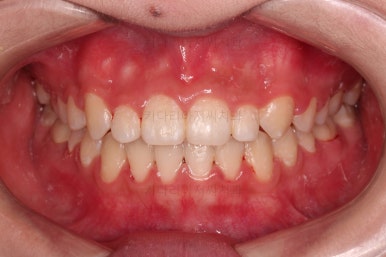

마찬가지로 초진 시 입안의 모습인데요.

위아래 앞니가 삐뚤고, 송곳니는 덧니처럼 불룩 튀어나가 있네요.

위아래 앞니는 안으로 굽어 들어와 있는 옥니(뻐드렁니 반대) 양상이었고요.

그리고 마무리 때 디테일에 문제가 생길 수 있는 부분인데, 윗니 대문니(가장 중간 치아)와 송곳니 사이의 치아를 작은 앞니라고 하는데요.

이 작은 앞니가 가져야 될 크기보다 더 작은 양상이었습니다.

이런 치아를 왜소치라교 표현합니다.

앞니 각도, 가지런한 느낌, 덧니 등 모든 점이 다 개선되었네요.

부산옥니교정 전후를 비교해 볼게요.

입안의 모습에서도 모든게 다 좋아졌고요.

웃는 모습과도 매우 조화롭게 치열이 가지런해졌네요.

앞니 각도가 개선되면서 웃을 때 보이는 치열도 가득차 보이고 환해보이고요.